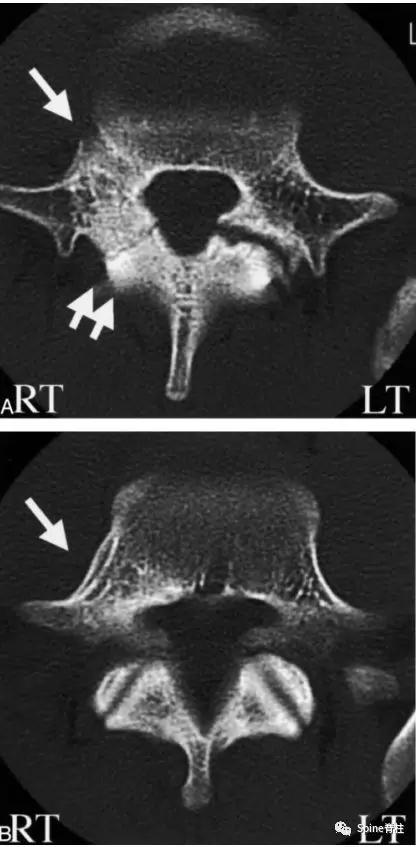

图:15岁腰痛男孩,左侧腰5椎弓根裂

A:T1左侧腰5椎弓根低信号(箭头);B:T2左侧腰5椎弓根高信号(箭头);C:T2轴位左侧腰5椎弓根骨折线明显,伴高信号区(箭头)。

图:起始CT提示L5左侧峡部裂(双箭头),起始CT检查后2个月复查可见出现右侧椎弓根裂(单箭头),4个月复查可见椎弓根裂愈合(单箭头)。

图:6个月复查可见右侧椎弓根裂已愈合(单箭头),但出现右侧峡部裂(双箭头)